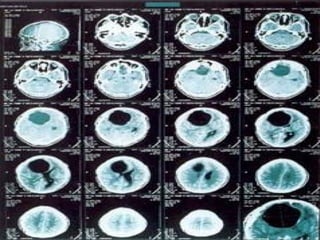

El documento describe una infestación por quistes larvarios de Taenia solium en un paciente que actuó como huésped intermediario al ingerir huevos del parásito. El paciente presentó múltiples lesiones musculares y cerebrales causadas por la degeneración y reacción inflamatoria de los quistes, incluyendo crisis convulsivas. El tratamiento incluyó prazicuantel y albendazol durante 15-30 días.